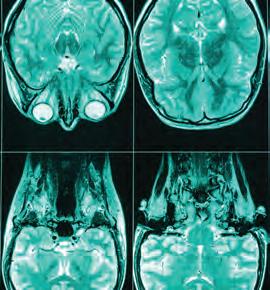

But the delay from disease onset to diagnosis is much longer than those few months, says Smita Saxena, a University of Missouri professor and NextGen Precision Health researcher with expertise in cellular neurosciences.

In that silent period before symptoms and diagnosis, the ALS disease process plays out in the body. A specific set of motor neurons may degenerate for years before the first physical signs show up, even while other brain cells function as normal. This phenomenon is called selective neuronal vulnerability, because only one set of neuronal cells is vulnerable to attack. It’s common across neurodegenerative diseases.

Saxena’s research is dedicated to understanding the phenomenon — and ultimately using that understanding not only to detect the disease earlier but also to develop better, more targeted therapies for a community of patients in need.